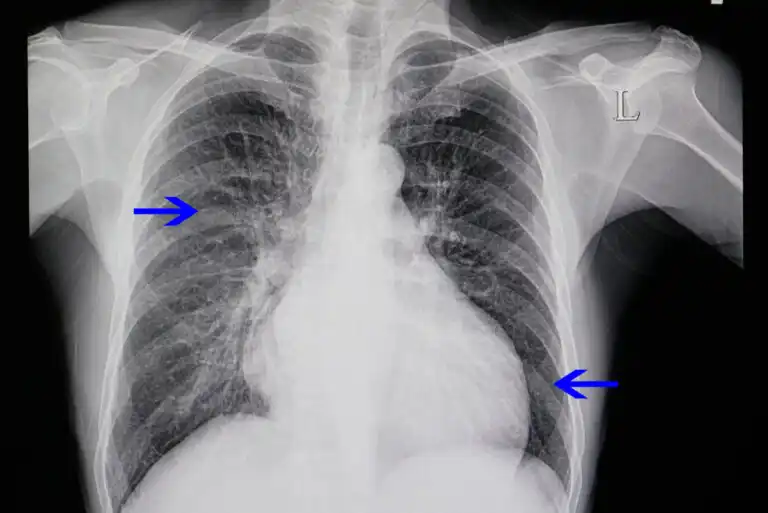

- تصوير الصدر بالأشعة السينية: باستخدام هذه التقنية يمكنك رؤية حالة الرئتين وحجم القلب. إذا ظهر متسعًا في الأشعة السينية ، فستكون هناك حاجة إلى اختبارات أخرى.